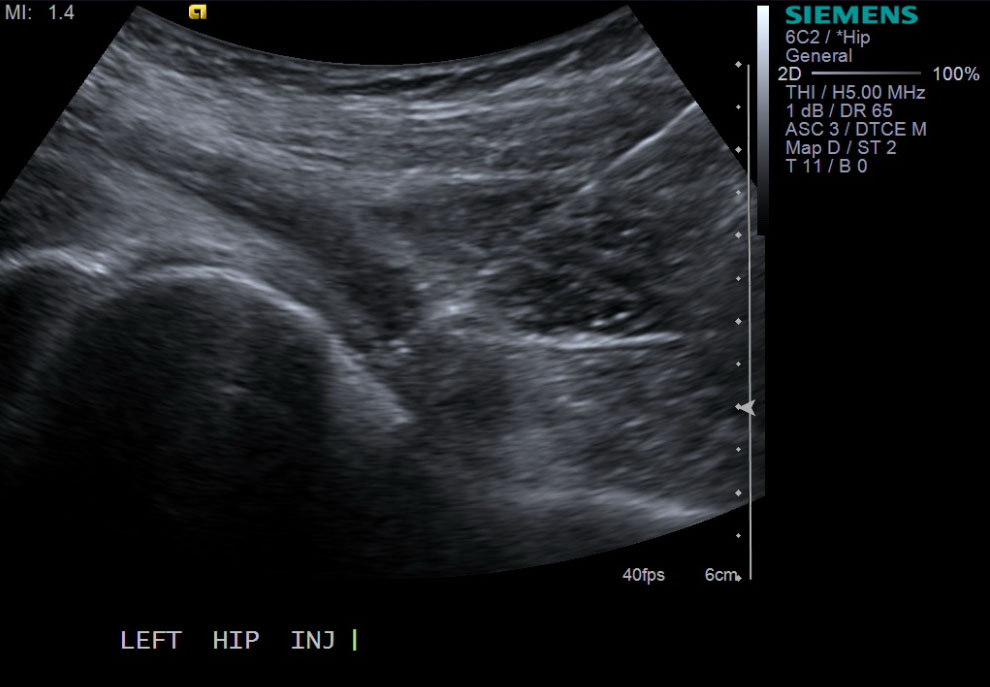

13. Scan joint to demonstrate distention. Can try to flex hip to see if fluid distended.

<